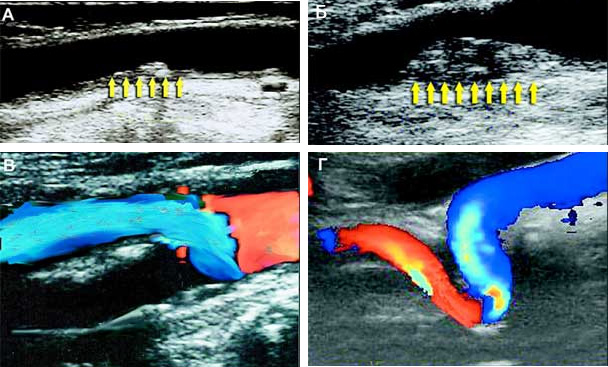

Широко используются для обследования больных не только в стационаре, но и в амбулаторных условиях ультразвуковые методы: допплерография и эхотомография, дуплексное сканирование и транскраниальная допплерография. Ультразвуковая допплерография применяется для выявления поражений сонных и позвоночных артерий. Она дает возможность получить информацию о профиле кровотока в сосудах. При дуплексном сканировании цветовое контрастирование потоков позволяет более четко разграничить движущийся (кровь) и неподвижные (стенки сосудов) объекты. Основные поражения сосудов, выявляемые методом транскраниальной допплерографии, — закупорки, стенозы, спазмы и аневризмы. Наиболее полную информацию о состоянии сосудистой системы мозга можно получить, сопоставив данные различных методов ультразвукового исследования. Недавно появился новый метод ультразвуковой диагностики — транскраниальная сонография с цветовым допплеровским кодированием. С его помощью можно «увидеть» структуры мозга через кости черепа.

У больных с грубыми сужениями магистральных сосудов головы (свыше 70%) решается вопрос о хирургическом вмешательстве. Под ним подразумеваются три вида операций: стентирование (расширение просвета сосуда с помощью специального каркаса — стента), реконструкция сосудистой системы (соединение различных сосудов между собой, формирование ответвлений) или удаление части сосуда и замена ее на протез.